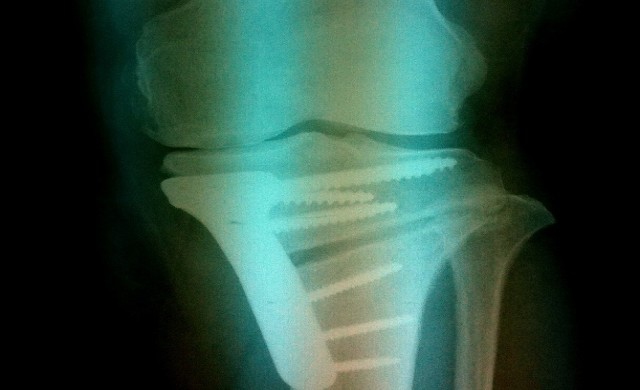

นพ.เจริญวัฒน์ อุทัยจรัสรัศมี ศัลยแพทย์ออร์โธปิดิกส์ ศูนย์การผ่าตัดเปลี่ยนข้อเข่าและข้อสะโพกเทียม (TJR Center ) โรงพยาบาลเวชธานี ได้ให้ข้อมูลว่า การใช้ระบบคอมพิวเตอร์นำวิถี ( Navigation assisted surgery) เข้ามาช่วยในการผ่าตัดเปลี่ยนข้อเข่าและข้อสะโพกเทียมในปัจจุบัน มีการพัฒนาอย่างต่อเนื่องและใช้กันมากขึ้น นอกจากนี้ ยังมีการคิดค้นซอฟต์แวร์ (Software) ที่สามารถนำมาประยุกต์ใช้ กับการผ่าตัดอีกชนิดหนึ่งซึ่งมีมานานแล้ว นั่นก็คือ การผ่าตัดแต่งแนวกระดูกหน้าแข้งส่วนบน (High tibial osteotomy - HTO) ซึ่งเป็นวิธีหนึ่งของการผ่าตัดรักษาผู้ป่วยโรคข้อเข่าเสื่อมในระยะเริ่มต้น ที่ข้อเข่ายังโก่งไม่มาก แต่ได้รับการรักษาด้วยยาแล้วไม่ได้ผล โดยการผ่าตัดรักษาโรคดังกล่าวจะใช้กับผู้ป่วยมีอายุไม่มากซึ่งมีอายุน้อยกว่า 60 ปี (< 60 ปี) แต่มีสุขภาพแข็งแรงดี และยังสามารถทำกิจวัตรประวันได้อยู่บ้าง (high demand activity)

"การผ่าตัดแต่งแนวกระดูกหน้าแข้งส่วนบน (High tibial osteotomy - HTO) ไม่ใช่การผ่าตัดรูปแบบใหม่ แต่เกิดขึ้นมานานแล้ว ก่อนการผ่าตัดเปลี่ยนข้อเข่าเทียมเสียอีก โดยมีเป้าหมายเพื่อปรับแนวการลงน้ำหนักของขาให้กลับมาใกล้เคียงภาวะปกติ โดยหวังที่จะให้เกิดการชะลอความเสื่อมของข้อเข่าส่วนที่มีความเสื่อมนั้นให้นานออกไป และลดการได้รับการผ่าตัดเปลี่ยนข้อเข่าเทียมก่อนเวลาอันควร"

ในอดีตการผ่าตัดด้วยวิธีดังกล่าวจำเป็นต้องมีการวางแผนก่อนทำการผ่าตัดหลากหลายขั้นตอน ซึ่งยุ่งยากและเสียเวลา อีกทั้งในระหว่างผ่าตัดยังมีโอกาสเกิดความผิดพลาดในการวัดมุมต่าง ๆ ได้ยาก ทำให้ผลการผ่าตัดอาจจะไม่ได้ตามที่ต้องการ รวมถึงการที่แพทย์และบุคคลากรในห้องผ่าตัดต้องสัมผัสกับรังสีที่เกิดจากการใช้ C arm หรือ Fluoroscopy เพื่อการดูภาพเอกซเรย์การตัดแต่งแนวกระดูกอย่างต่อเนื่อง เป็นเวลานาน ปัญหาต่างๆเหล่านี้จะลดลงเมื่อมีการนำระบบคอมพิวเตอร์มาช่วยในการผ่าตัด ( Navigation assisted high tibial osteotomy : NAV-HTO)